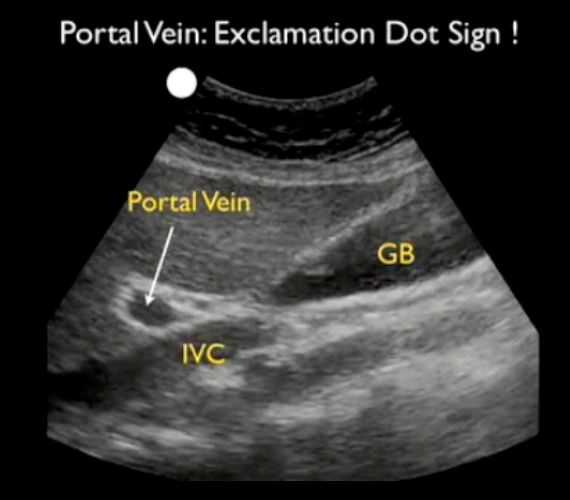

What is the name of this sign? What structures are involved?

Exclamation point sign.

Gallbladder, portal vein, liver, IVC.